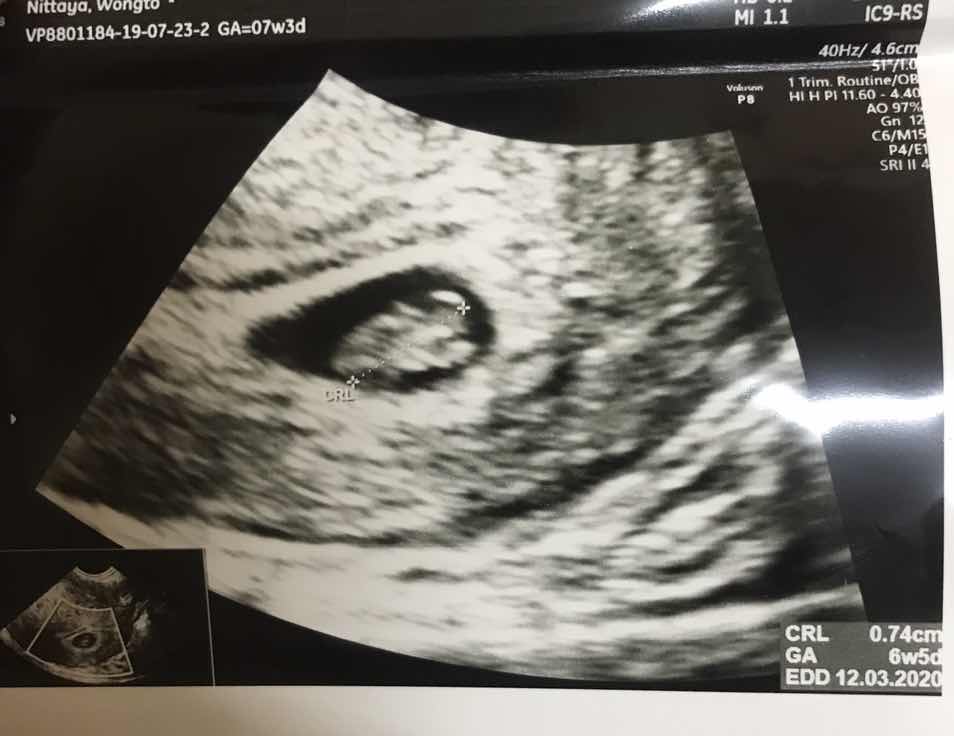

ท้องได้7สัปดาห์เห็นตัวลูกยังค่ะ

คือเราท้องได้7สัปดาห์แล้ว อัลตราซาวนด์มีแค่ถุงในมดลูกแต่ยังไม่มีตัวเด็ก แบบนี้ผิดปกติไหมค่ะ

เห็นแล้วค่า แต่ยังเล็ก ของเราเห็นตั้งแต่ 6w5d คะ